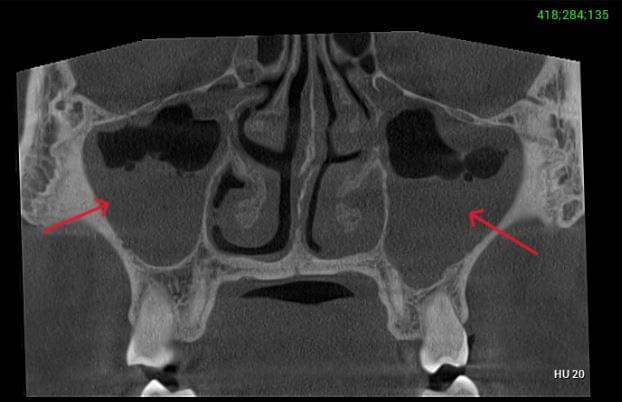

Діагностика гайморових пазух за допомогою КТ

У сучасній медицині КТ придаткових пазух носа (або КТ синусів) — це «золотий стандарт»

діагностики для ЛОР-лікарів та щелепно-лицевих хірургів. Звичайний рентген часто не

показує повну картину, а МРТ не завжди доступний і дорожчий. Комп’ютерна томографія дає

детальну 3D-модель усіх пазух (гайморових, лобних, клиновидних та решітчастого

лабіринту) за 10 секунд і з мінімальною дозою опромінення.

КПКТ (конусно-променева комп’ютерна томографія) — це 3D-знімок високої роздільної здатності. На відміну від звичайного рентгену, КТ показує: